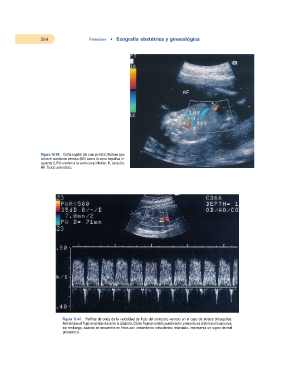

Figura 12-46. Corte sagital del cuerpo fetal. Nótese que

tanto el conducto venoso (DV) como la vena hepática iz-

quierda (LHV) vierten a la vena cava inferior. H, corazón;

AF, fluido amniótico.

Figura 12-47. Perfiles de onda de la velocidad de flujo del conducto venoso en el caso de atresia tricuspídea.

Adviértase el flujo invertido durante la diástole. Dicho flujo invertido puede estar presente en distintas situaciones;

sin embargo, cuando se encuentra en fetos con crecimiento intrauterino retardado, representa un signo de mal

pronóstico.